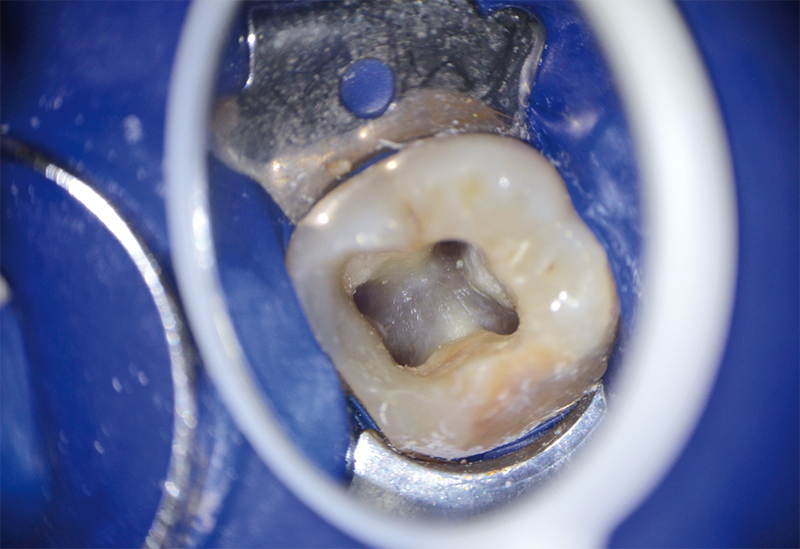

Plus récemment, des cavités endodontiques conservatrices ont été dé­crites afin de limiter l’élimination des structures, préserver un maximum de dentine pericervicale et une partie du plafond pulpaire, ouvert au minimum pour permettre la visualisation des canaux depuis un seul point de vue. L’aide de la tomosynthèse volumique (CBCT) a même été décrite pour identifier la situation des canaux et optimiser la forme de la cavité à réaliser. Ce concept a été poussé à l’extrême avec la réalisation de cavités ultraconservatrices aussi appelées « cavités ninja » qui se limitent à une ouverture minimisée du plafond pulpaire permettant l’accès et la visualisation des différents canaux depuis des angles de vue différents.

Les auteurs de cette étude ont voulu évaluer la résistance à la fracture des dents cuspidées dépulpées avec des CAE classiques, conservatrices et utraconservatrices (ninja). Cent soixante molaires et prémolaires récemment extraites ont été équitablement réparties en quatre groupes dont un groupe contrôle (dents intactes) et un groupe pour chacun des trois types de CAE. Pour ceux-ci, les dents ont subi un traitement endodontique complet puis ont été restaurées à l’aide de résine composite. Un test mesurant la charge jusqu’à la fracture a été réalisé sur chaque dent, et le type de fracture résultant a été observé. Les résultats montrent que la force moyenne engendrant la fracture est significativement plus basse pour les CAE traditionnelles que pour les cavités conservatrices, ultraconservatrices et les dents intactes sans différence significative entre ces trois dernières catégories. Les dents avec cavités « ninja » ultraconservatrices ne sont pas plus résistantes à la fracture que les dents avec cavités conservatrices. Par ailleurs, les fractures induites sur les dents intactes sont souvent restaurables, tandis que les dents préparées présentent plus souvent des fractures compromettant la survie de la dent, car situées sous la jonction amélo-cémentaire.

La principale difficulté est la visualisation de l’ensemble du plancher pulpaire, donc la location de toutes les entrées canalaires. L’emploi d’aides optiques est indispensable pour aborder ce type de cavité. Par ailleurs, les contraintes coronaires engendrées sur les instruments compliquent davantage la mise en forme canalaire.